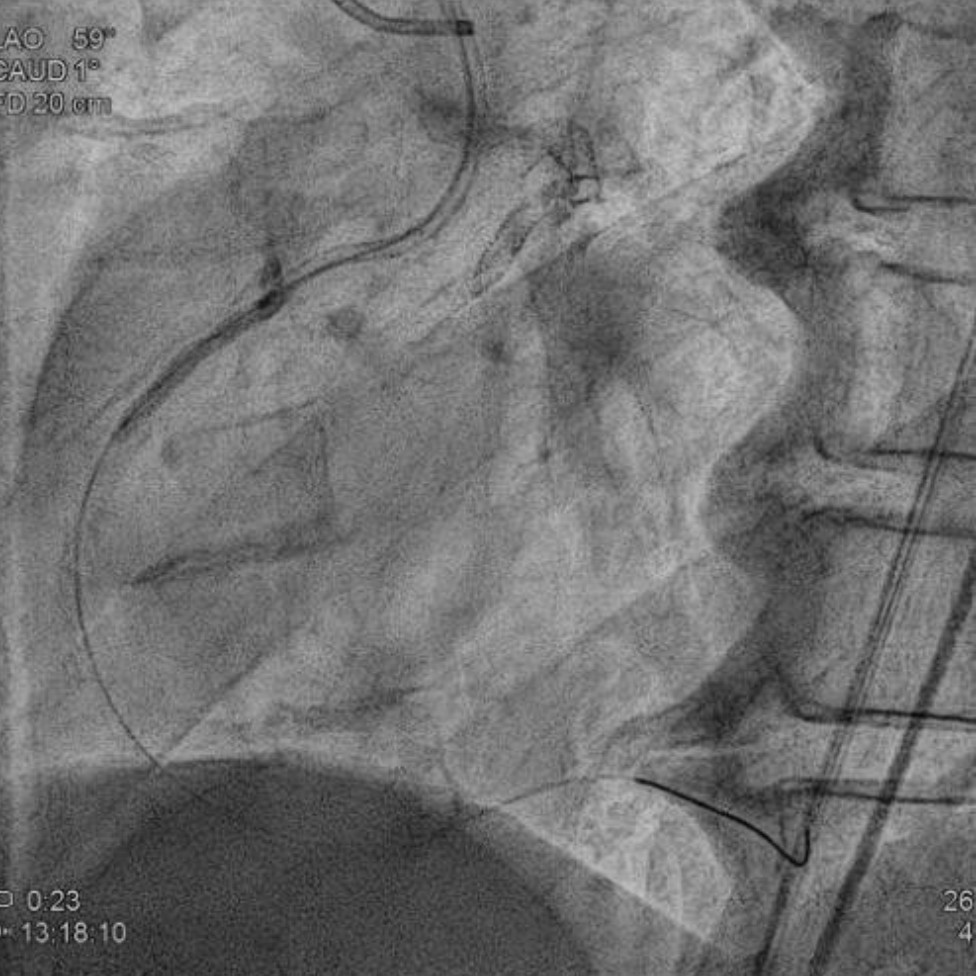

We advanced a 6F JR 4.0 SH 100cm guiding catheter and crossed the RCA ostial lesion using a Fielder FC guidewire. Pre-dilatation was performed with Ryurei 1.5¡¿15mm balloon. IVUS was then performed, revealing a patent stent in the proximal to mid RCA. However, the ostial RCA stent was under-expanded, with smooth muscle compressing the stent from outside. Balloon pre-dilatation was carried out using an NC Euphora 4.0¡¿12mm balloon, inflated up to 22 bar. However, the lesion was resistant and could not be fully dilated. We then applied a 4.0mm intravascular lithotripsy balloon with a total of 100 shocks delivered. But the effect was still minimal. The IVUS showed limited additional plaque fracture or vessel expansion. We tried NC Sapphire II 4.5¡¿8 mm balloon inflation to 18 bar, but it was ineffective due to balloon slippage. The angiogram after oversized NC dilation showed residual stenosis of 59%. We then selected a Wolverine Cutting Balloon 4.0¡¿10 mm and initiated dilation to 6 bar, which resulted in easy slippage again. Subsequent oversized dilations were performed at 18 bar, after which the lesion was successfully dilated. Using a Runthrough Floppy guidewire with the floating wire technique, a drug-eluting stent Biofreedom Ultra 4.0¡¿14 mm was deployed in the ostial RCA ISR. We inflated at 14 bar for 14 seconds, repeated twice. Final post-dilatation was performed with an Accuforce 4.0¡¿15mm balloon. The final IVUS showed good stent placement and expansion. We closed the procedure.